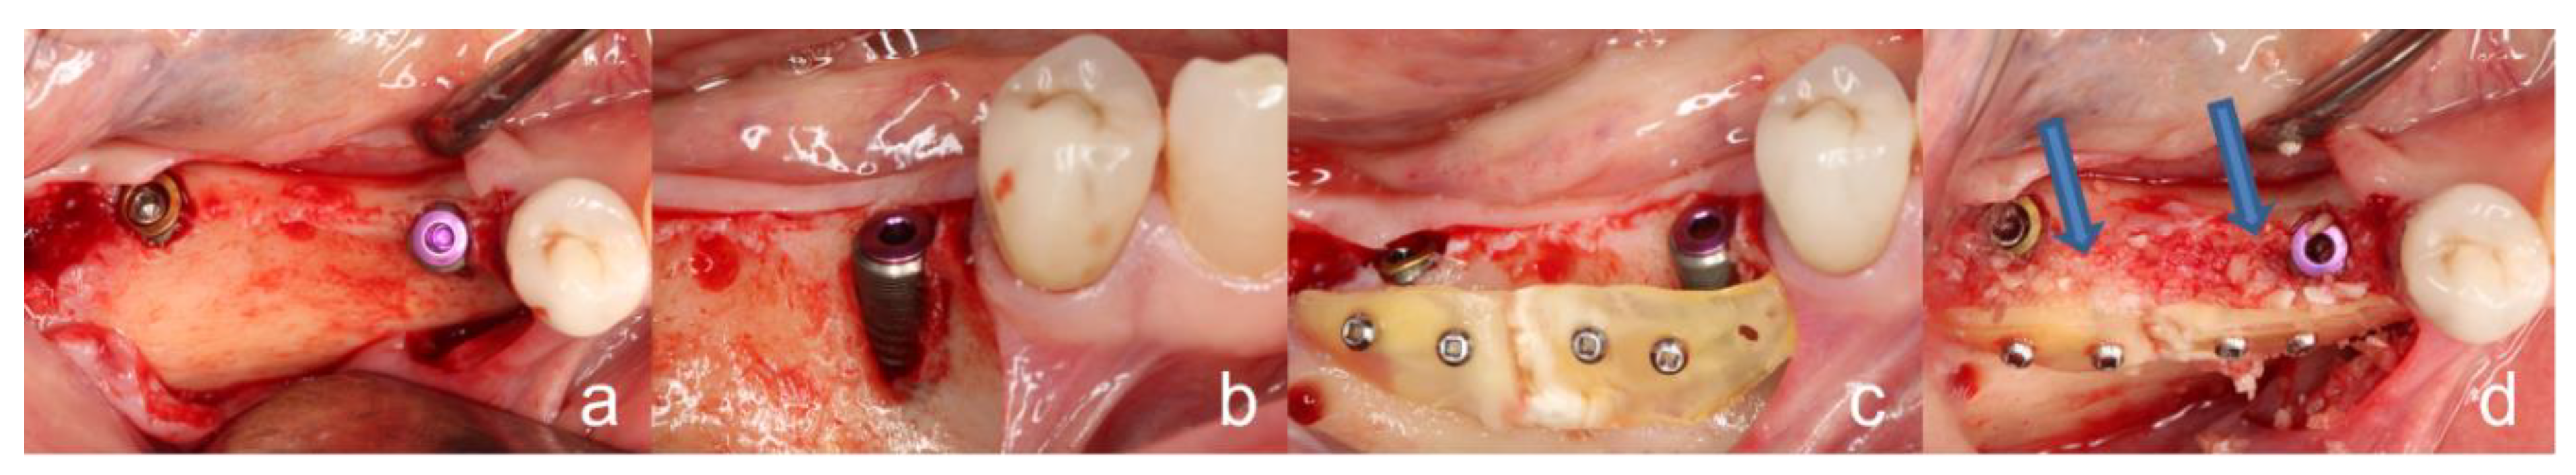

2.4. Surgical Procedure of the Tooth Shell Technique (TST)